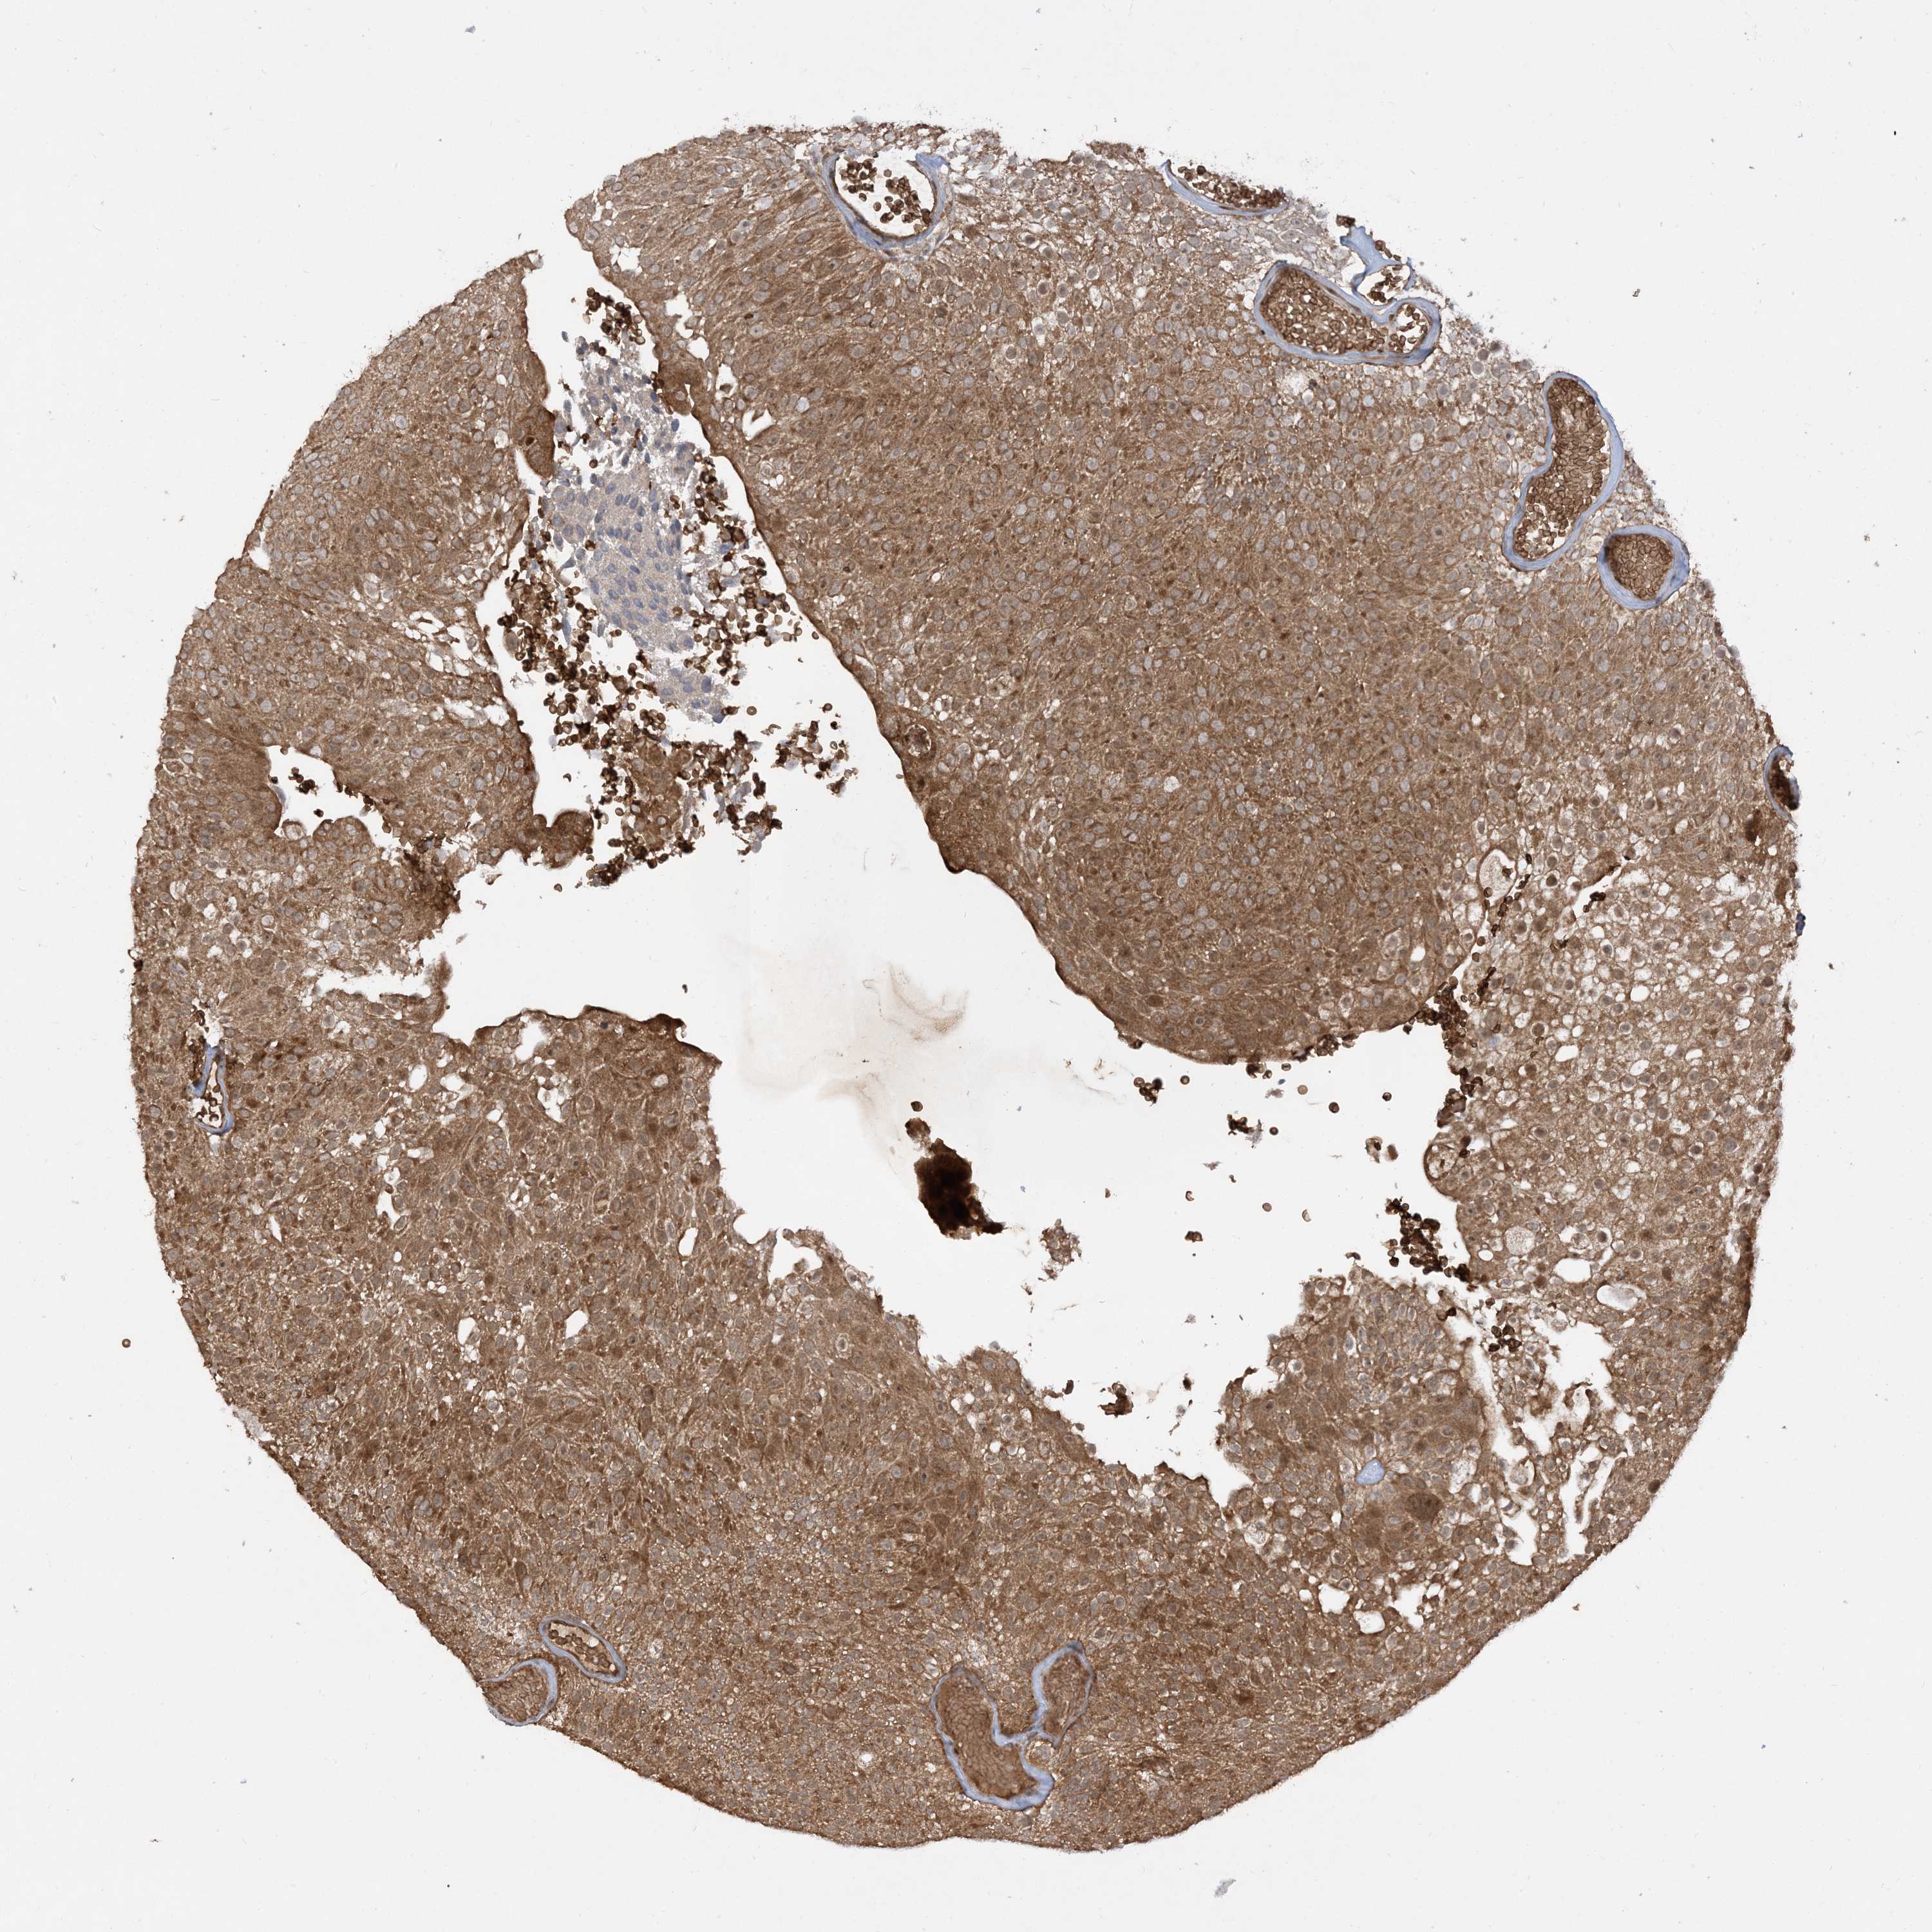

UROTHELIAL CANCER - Protein expressioni

A mouse-over function shows sample information and annotation data. Click on an image to view it in a full screen mode. Samples can be filtered based on level of antibody staining by selecting one or several of the following categories: high, medium, low and not detected. The assay and annotation is described here.

Note that samples used for immunohistochemistry by the Human Protein Atlas do not correspond to samples in the TCGA dataset.

Antibody stainingi

Antibody staining in the annotated cell types in the current human tissue is reported as not detected, low, medium, or high, based on conventional immunohistochemistry profiling in selected tissues. This score is based on the combination of the staining intensity and fraction of stained cells.

Each image is clickable and will lead to virtual microscopy that enables deeper exploration of all samples and also displays staining intensity scores, fraction scores and subcellular localization as well as patient and tissue information for each sample.

Antibody HPA032057

Staining

High

Medium

Low

Not detected

Intensity

Strong

Moderate

Weak

Negative

Quantity

>75%

75%-25%

<25%

None

Location

Nuclear

Cytoplasmic/membranous

Cytoplasmic/membranous,nuclear

Urothelial carcinoma, Low grade

Urothelial carcinoma, High grade